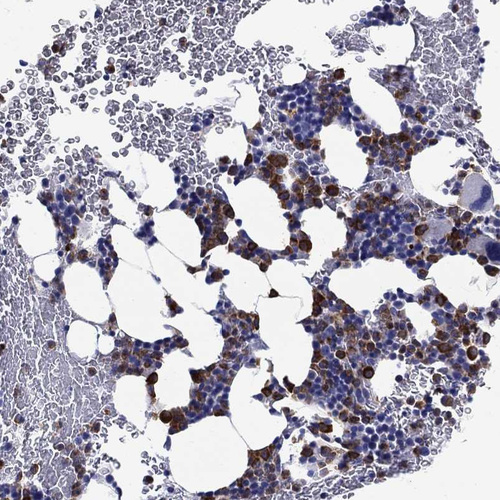

Immunohistochemistry analysis in human bone marrow and testis tissues using HPA076792 antibody. Corresponding EPX RNA-seq data are presented for the same tissues.